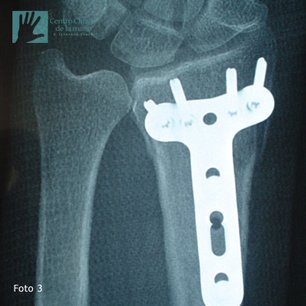

Fractura de Muñeca